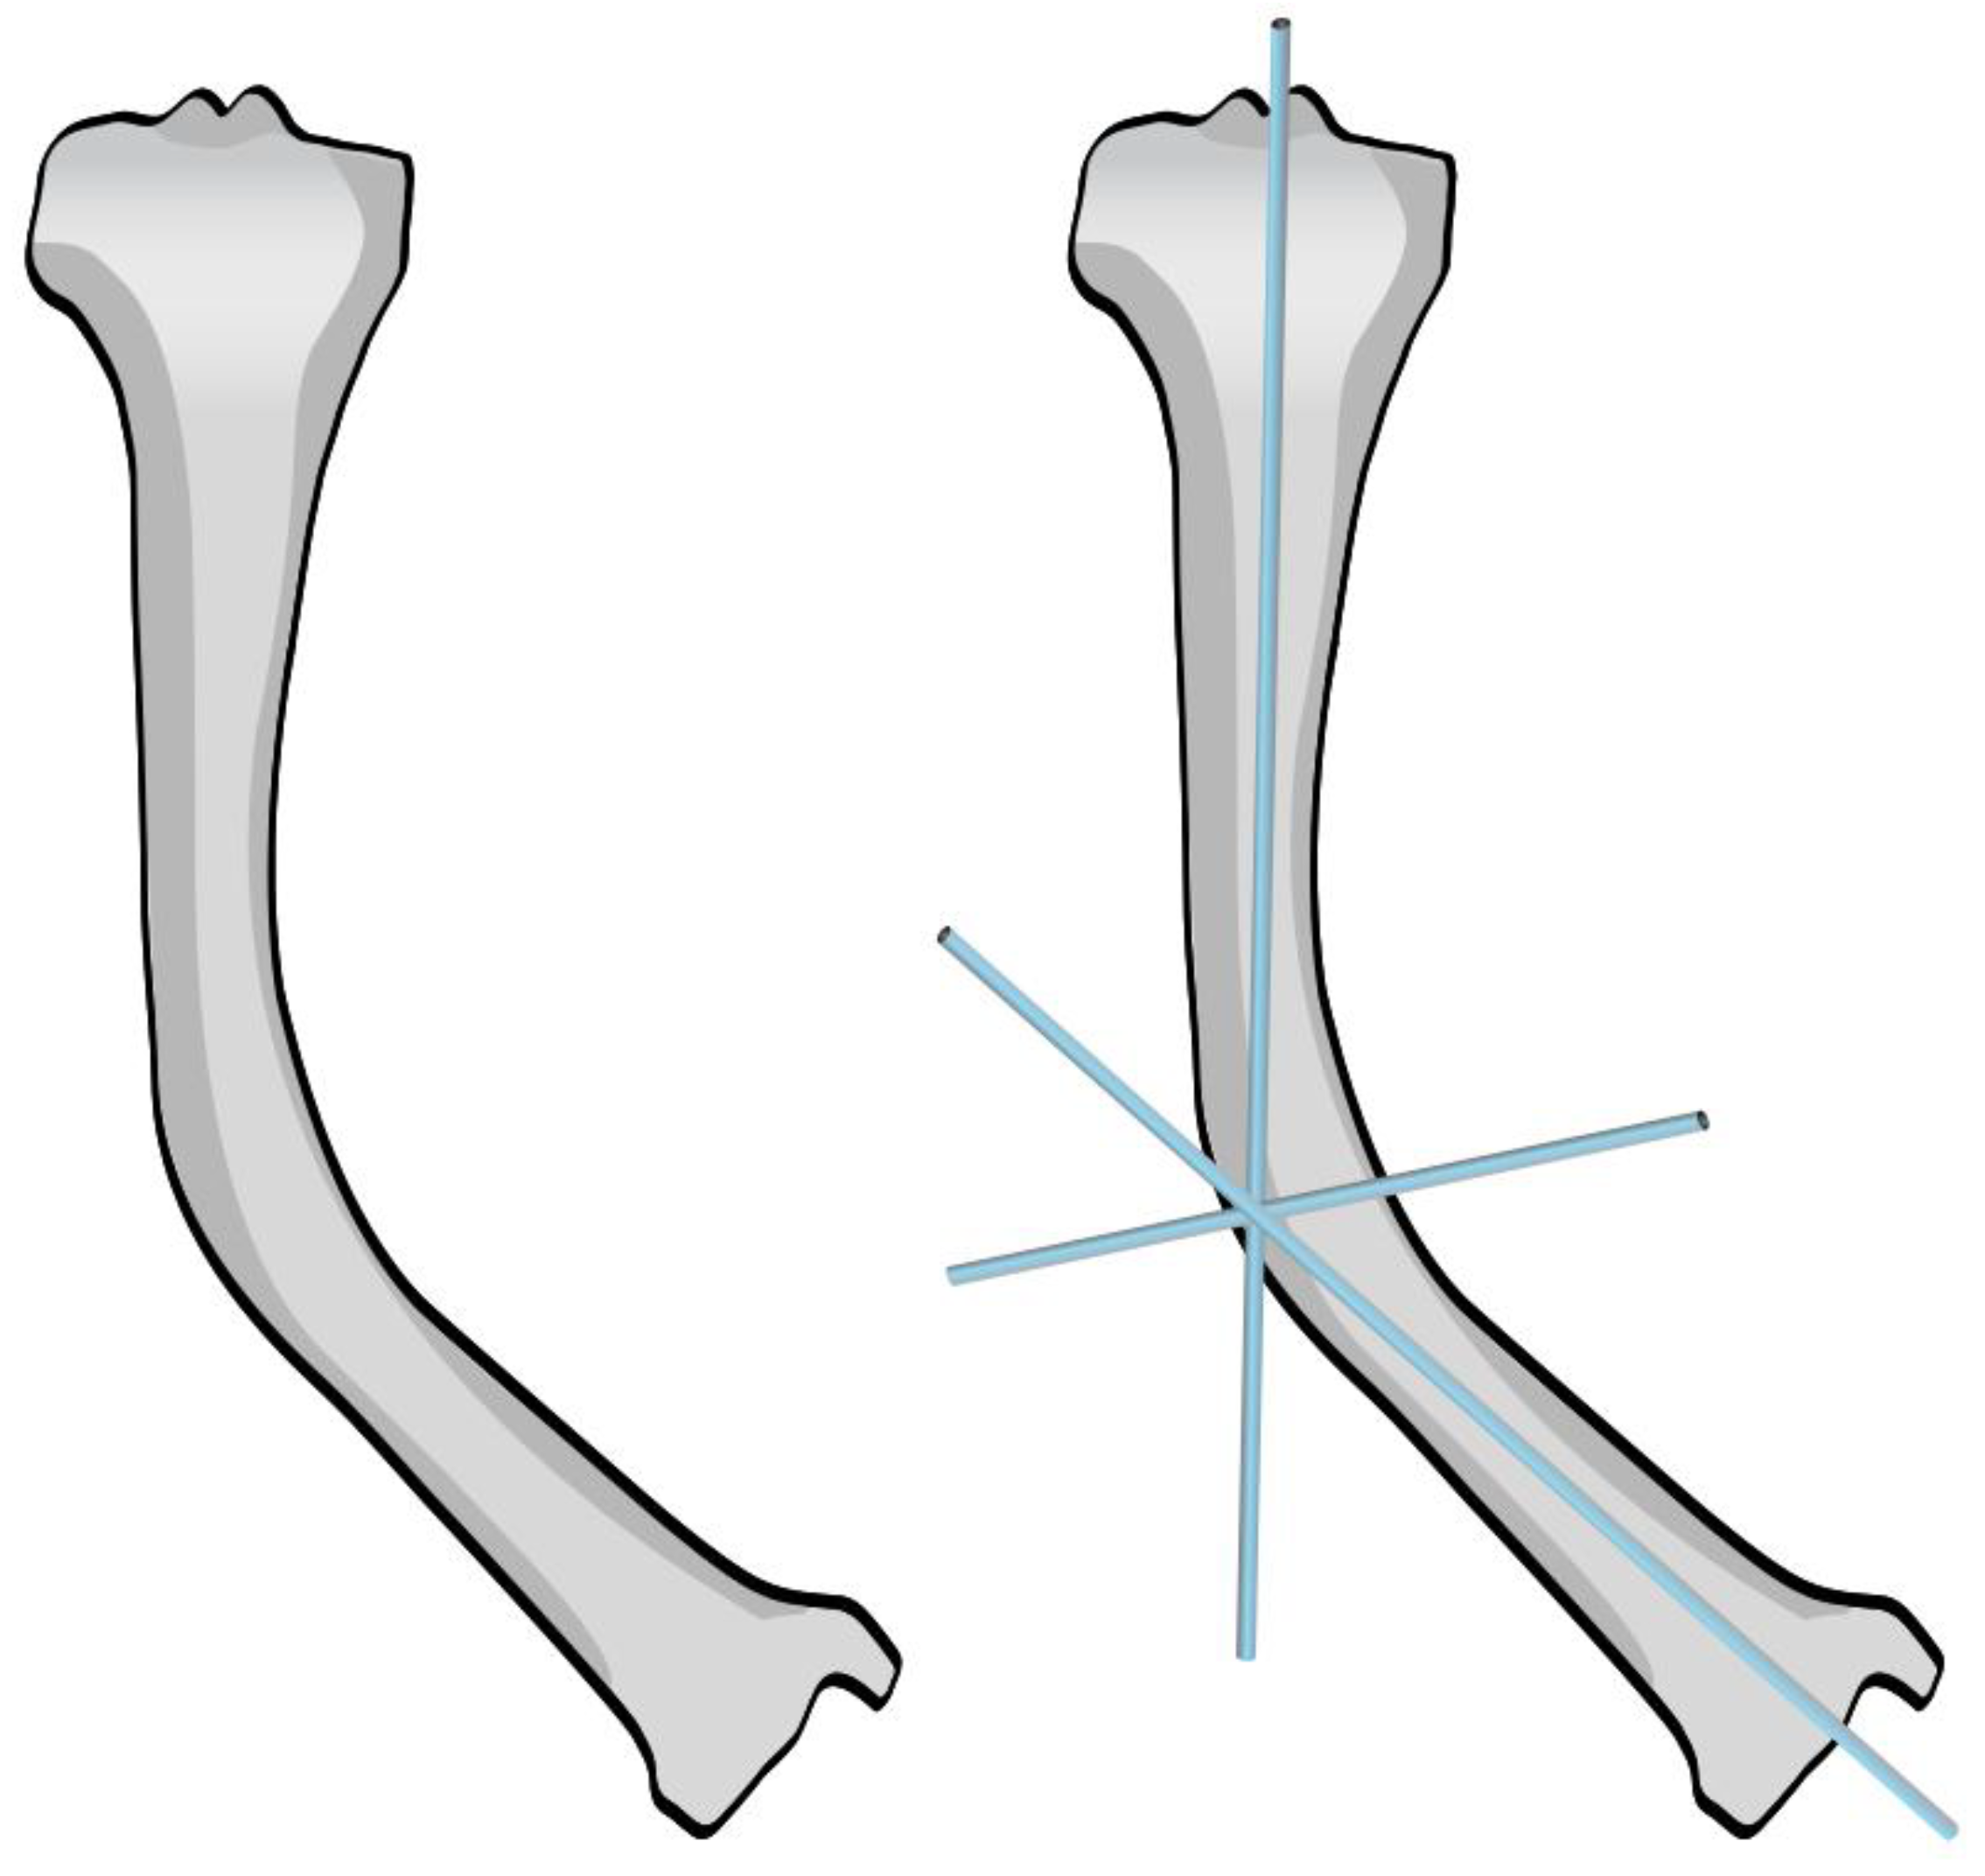

Figure 14. Post-operative X-ray showing SLIM nail and plate.

In the third case, a 16-year-old skeletally mature patient with OI was scheduled to undergo revision from FD rod to SLIM nail after presenting with pain due to stress fractures and wild deformity in his proximal right femur (Figure 11). The FD rod was removed, and then, using a piriformis entry point, access to the femur and proximal reaming was done. There were two CORAs; the first CORA was identified in the subtrochanteric region, and a percutaneous osteotomy technique was done to realign the bone, and then reaming was continued (Figure 12). The second CORA was identified, and another percutaneous osteotomy was done, and the bone was cracked with a closed osteoclasis technique, and then reaming was continued in the distal segment (Figure 13). The SLIM nail was then inserted and had an excellent fit. The subtrochanteric region was under high stress, so a 2.7 Smith and Nephew EVOS plate to further stabilize the segment and control the rotation. Two screws were placed above and below (Figure 14). In this case, the indication for the use of the SLIM nail was the need to revise the existing telescoping FD rod in a skeletally mature patient to a solid nail. As the intramedullary canal was too small to accommodate a larger solid nail, a SLIM nail was used instead. The use of a plate as an adjunct to an intramedullary nail is also shown.